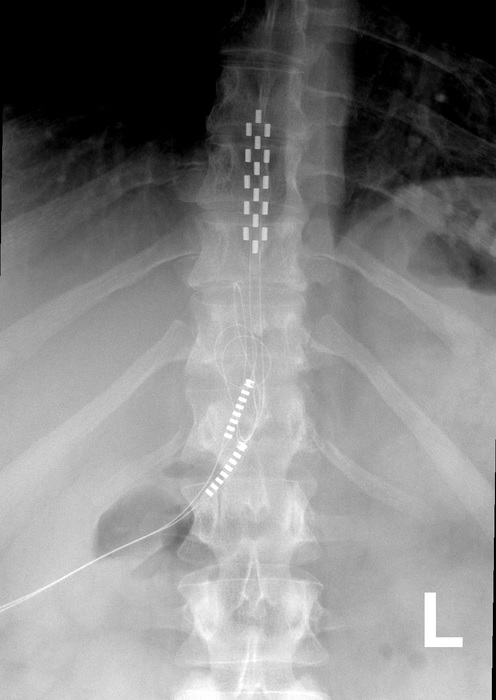

Radiographie d’une colonne vertébrale humaine avec implant stimulateur de moelle épinière. Crédit. Mconnell, CC BY 3.0, via Wikimedia Commons https://commons.wikimedia.org/wiki/File:Anterior_thoracic_SCS.jpg

On pense que la stimulation de la moelle épinière fonctionne en implantant un dispositif qui envoie des impulsions électriques à la moelle épinière pour interrompre les signaux nerveux avant qu’ils n’atteignent le cerveau.